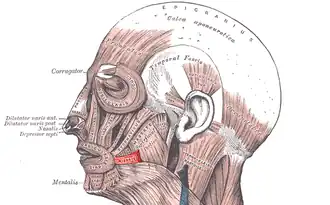

Muscles of the head, face, and neck. Risorius shown in red. This is the most standard version of the direction and origin of the muscle. | |